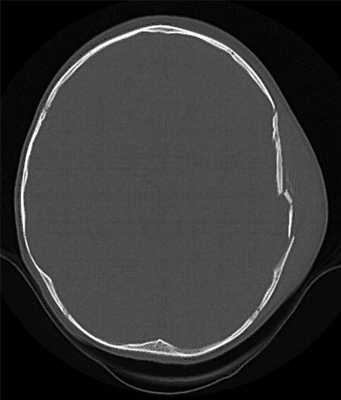

Наиболее показательны 2 случая расхождения — с ложноотрицательным и ложноположительным результатом. В первом случае в стационаре не был диагностирован перелом костей свода и основания черепа (перелом теменной кости с переходом на затылочную). При ретроспективном анализе результатов КТ, записанных на оптических носителях, врач-рентгенолог в режиме мультипланарной реконструкции (создание двухмерных изображений в различных произвольных плоскостях) также не обнаружил перелом. Только в режиме трехмерной реконструкции с созданием объемных изображений повреждение было визуализировано (рис. 1, 2).

Рис. 1. Трехмерная реконструкция черепа (стрелкой указан перелом). Рис. 2. Перелом теменной и затылочной костей. Во 2-м случае в стационаре диагностировали переломы скуловой дуги, стенок глазницы (в том числе верхней стенки верхнечелюстной пазухи) с той же стороны, и носовых костей. В этой же зоне имелись косвенные признаки травмы (обширный кровоподтек лица), однако какое-либо содержимое в верхнечелюстной пазухе отсутствовало. При ретроспективном анализе в режиме мультипланарной реконструкции у специалиста возникли подозрения о наличии переломов. При трехмерной реконструкции каких-либо повреждений не выявили, что полностью совпадает с результатами вскрытия. Имевшиеся деформации костей, симулировавшие их повреждения, следовало рассматривать как анатомические особенности, на что косвенно указывало отсутствие содержимого в верхнечелюстной пазухе. Таким образом, рентгенологи стационаров, располагая технической возможностью использовать различные режимы визуализации, могли не только диагностировать обнаруженные на вскрытии повреждения черепа, но и верно интерпретировать анатомические особенности.